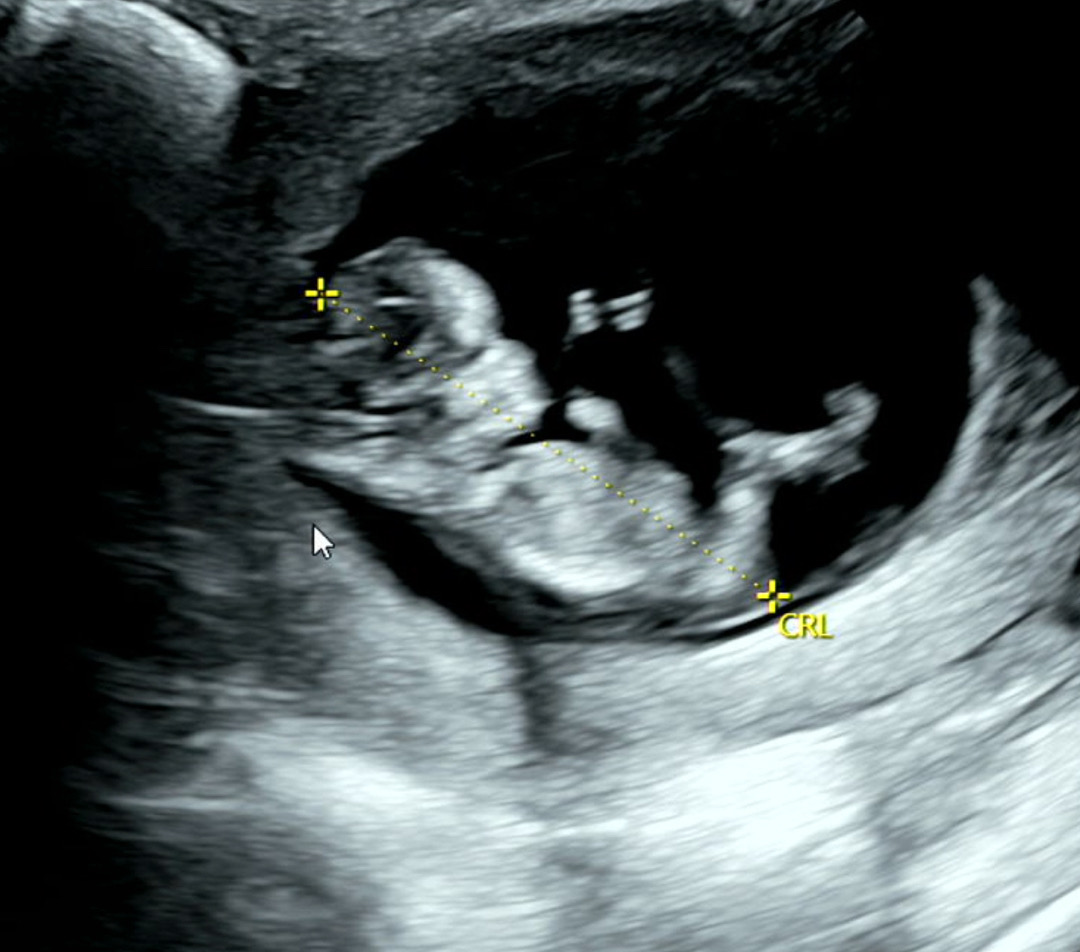

각도법 ?

내일이면 13주차 시작되네요 거의 16주에 병원 예약이 잡혀서 멀게만 느껴져요 ㅎㅎ 각도법으로 본 성별은 어떤가요 ? 원하는 성별은 없습니당